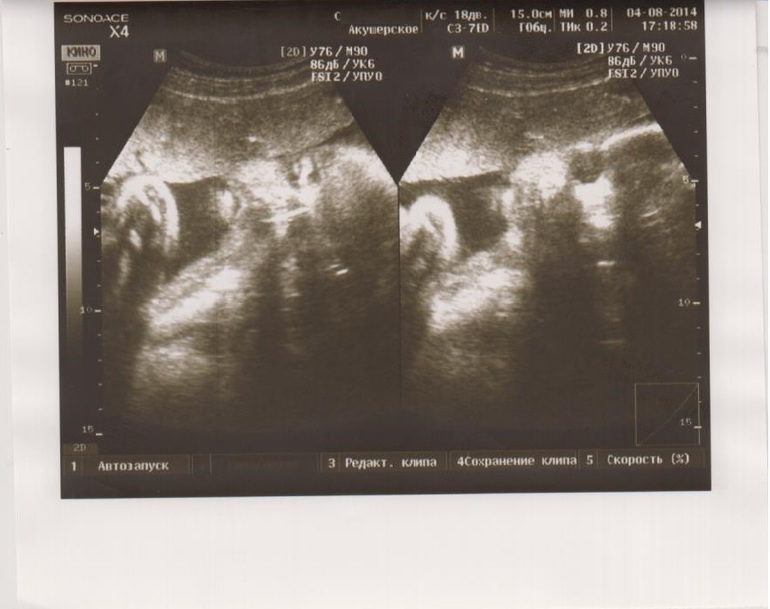

В общем все замеры записала, потом мне рассказывает, что наш кабанчик поросёнок на 31 неделю, обхват головы 80,8, вес 1500 кг. Кол-во вод нормальное. Ножки-ручки тоже с опережением графика. Лежит головкой вниз, обвития нет.

И наш портретик (с закрытыми и открытыми глазками)